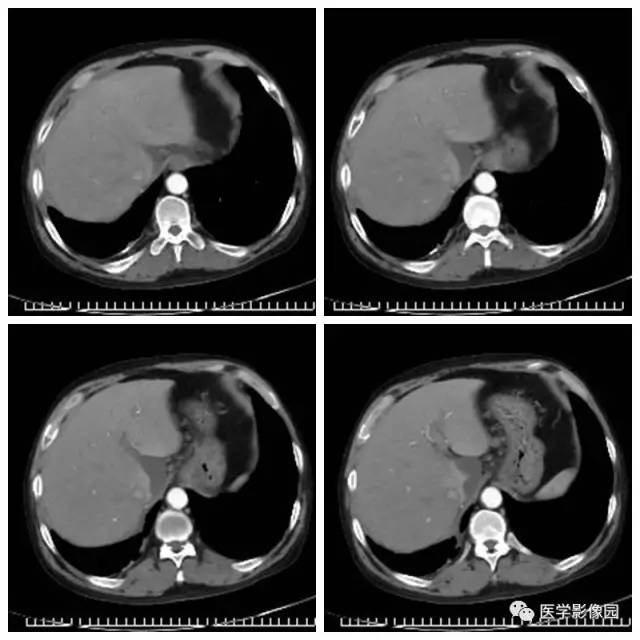

非霍奇金淋巴瘤影像-医学影像图,_医学图库

腹腔及腹膜后多发肿大淋巴结,会是什么呢

腹腔及腹膜后多发肿大淋巴结,会是什么呢